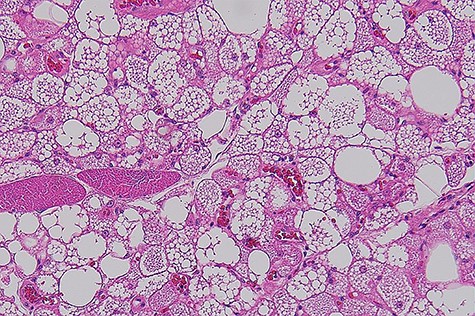

Macroscopically, it was a fatty mass measuring 48 × 39 × 35 mm, which on cross-section did not reveal any necrosis, haemorrhagic or fibroseptae formation. Microscopically the lesion was composed of lobules of brown far with abundant macrovesicles (Fig. 2). There was no evidence of increased mitotic activity or necrosis. There were no infiltrative borders on the lesions. Fluorescence in situ hybridization was used for assessment of MDM2 gene (12q15) amplification, which was negative. This was performed to rule out any atypical lipomatous tumour.

Histophotograph showing lobules of fat with multivaculated brown fat cells without evidence of dysplasia or necrosis.